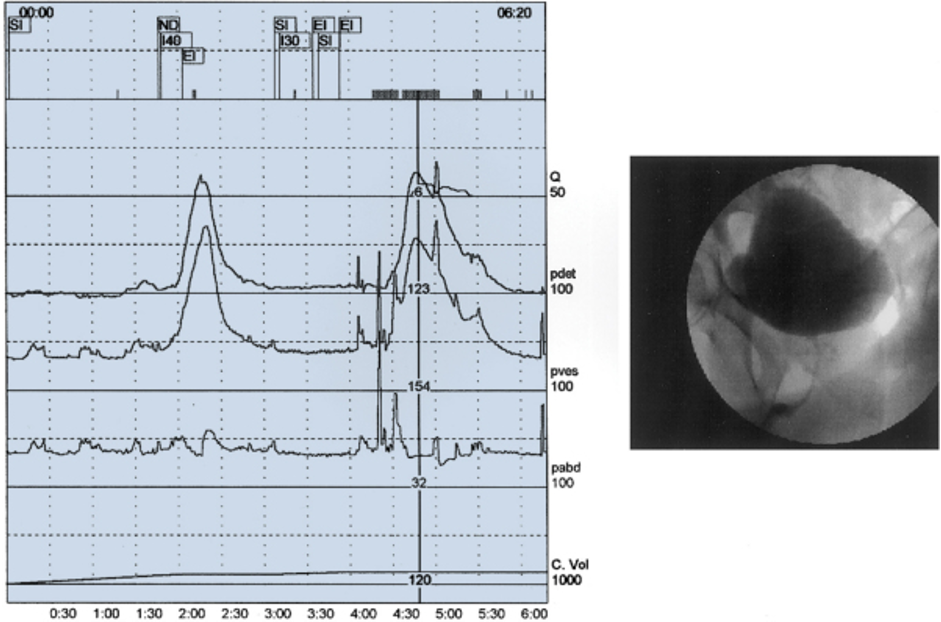

Videourodynamics

- Definition: The simultaneous display of bladder and urethral pressures with fluoroscopic imaging of the lower tract is videourodynamics.

- It is the most sophisticated form of evaluation of patients with complex urinary tract dysfunction.

- This is desirable when simultaneous evaluation of structure and function is necessary to make a diagnosis

- Videourodynamics is useful to identify the specific site of the obstruction as being at the bladder neck, the prostatic urethra, or the distal sphincter mechanism